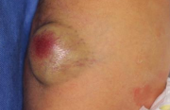

6. 血管腫、リンパ管腫

一般的に赤くみえるあざを血管腫と呼んでいますが、血管の内皮細胞が増殖している乳児血管腫(苺状血管腫)と血管が拡張していたり、走行が異常であったりする血管奇形(単純性血管腫、海綿状血管腫など)に分けられます。苺状血管腫は生後1週間から1ヵ月以内に出現し徐々に大きくなってきますが、単純性血管腫、海綿状血管腫は生まれた直後からあって、血流量によって大きさや色は変化します。

苺状血管腫は通常 3 歳までに小さくなってくるので、急いで治療をする必要はありませんが、ある程度の大きさがあり増大傾向を示していたり、目を塞いでいるなど将来的に機能的な障害を残したり、顔面に醜状変形を残す可能性がある場合には飲み薬での治療を行う事があります。また、3歳をすぎても目立つ膨らみや赤さが残る場合は、手術による切除やレーザー治療を行う事があります。

真皮内の毛細血管が拡張した単純性血管腫ではレーザー治療の適応となりますが、皮下の太い静脈などが拡張した海綿状血管腫などではレーザー治療は難しく手術治療が必要となります。 その他には血管以外の脈管奇形にリンパ管腫があります。

苺状血管腫は通常 3 歳までに小さくなってくるので、急いで治療をする必要はありませんが、ある程度の大きさがあり増大傾向を示していたり、目を塞いでいるなど将来的に機能的な障害を残したり、顔面に醜状変形を残す可能性がある場合には飲み薬での治療を行う事があります。また、3歳をすぎても目立つ膨らみや赤さが残る場合は、手術による切除やレーザー治療を行う事があります。

真皮内の毛細血管が拡張した単純性血管腫ではレーザー治療の適応となりますが、皮下の太い静脈などが拡張した海綿状血管腫などではレーザー治療は難しく手術治療が必要となります。 その他には血管以外の脈管奇形にリンパ管腫があります。

形成外科では倫理委員会の承認を受け、出血を繰り返していたり潰瘍を形成していたりする症例、機能的な障害や醜状変形を残す可能性が高い症例などに限り、血液腫瘍科と協力して乳児血管腫に対するプロプラノロール内服療法を行なっています。

右前腕の乳児血管腫

背中の乳児血管腫